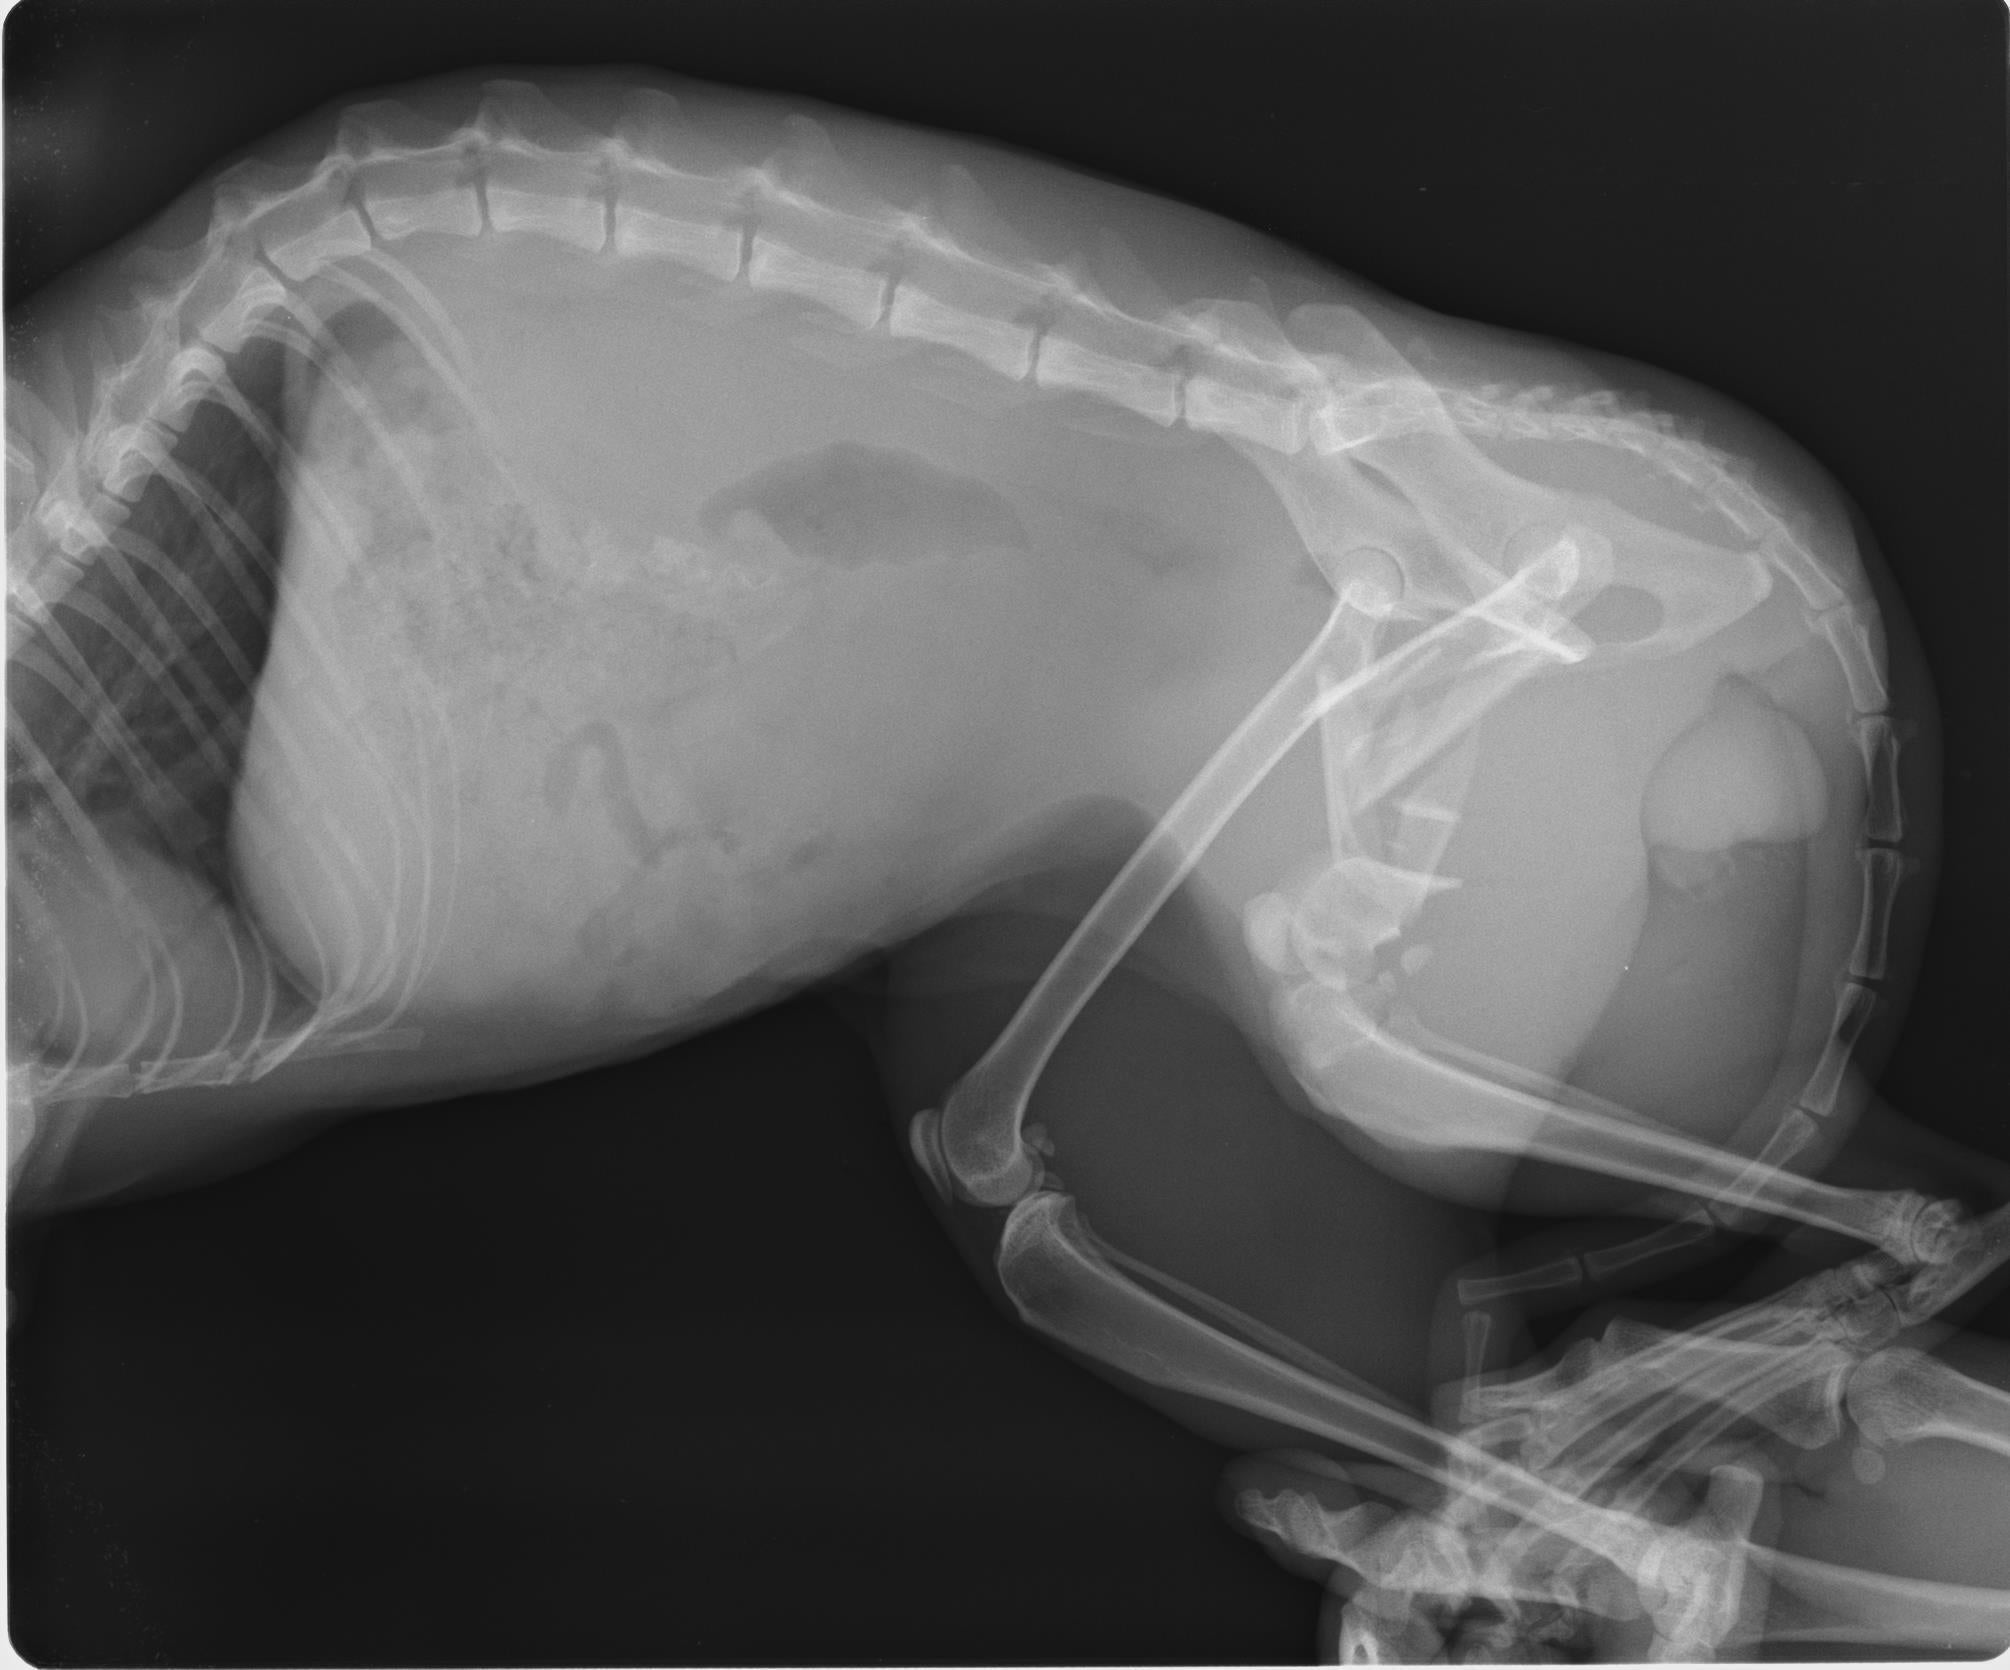

◯左側大腿骨複雑骨折

診断結果:骨盤骨折 / 左大腿骨複雑骨折 / 肺挫傷 / 猫エイズ陽性

精密検査をし、骨盤骨折は現状維持&要経過観察

左側大腿骨はかなりひどい粉砕骨折だが、プレートを入れる手術を行い四足歩行できる状態を目指し、手術決行